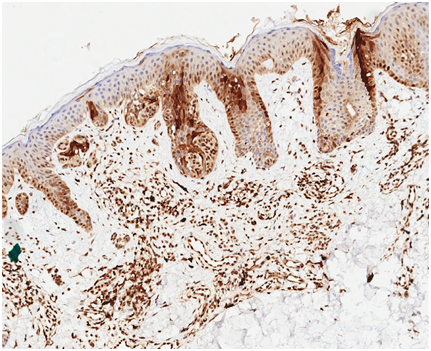

Following institutional review board-authorization, 13 primary cutaneous melanomas and 19 nevi were retrieved (5 common nevi, 5 mild dysplastic, 4 moderate dysplastic, and 5 severe dysplastic), (Figures 1-3). 5-μm formalin-fixed, paraffin-embedded sections were cut and mounted onto positively charged slides. Single IHC S100A9 staining was performed using the Leica Bond III protocol. All antibodies were purchased from Leica Biosystems (Buffalo Grove, IL). A board certified dermatopathologist evaluated S100A9 staining of melanocytes and keratinocytes in the epidermis of each sample. The pattern of staining was classified according to one of three categories: diffuse epidermal staining Figure 4, linear basement membrane staining Figure 5, and irregular patchy epidermal staining Figure 6.

Figure 4 Diffuse epidermal S100A9 stain of malignant melanoma in situ of lesion A.